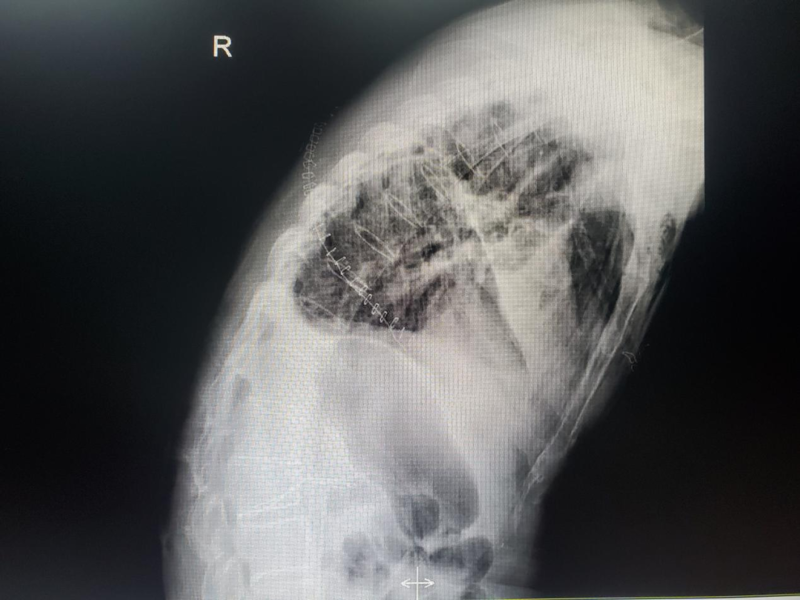

▲DR侧位片显示胸椎曲度变直,椎旁韧带增厚,小关节融合